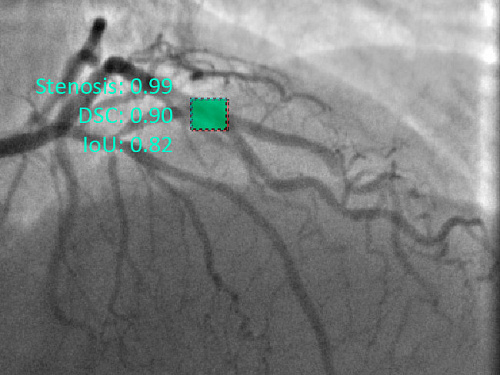

Нейронные сети научились лучше искать сужения кровеносных сосудов

Международный коллектив ученых разработал алгоритм, который находит сужения кровеносных сосудов серд...